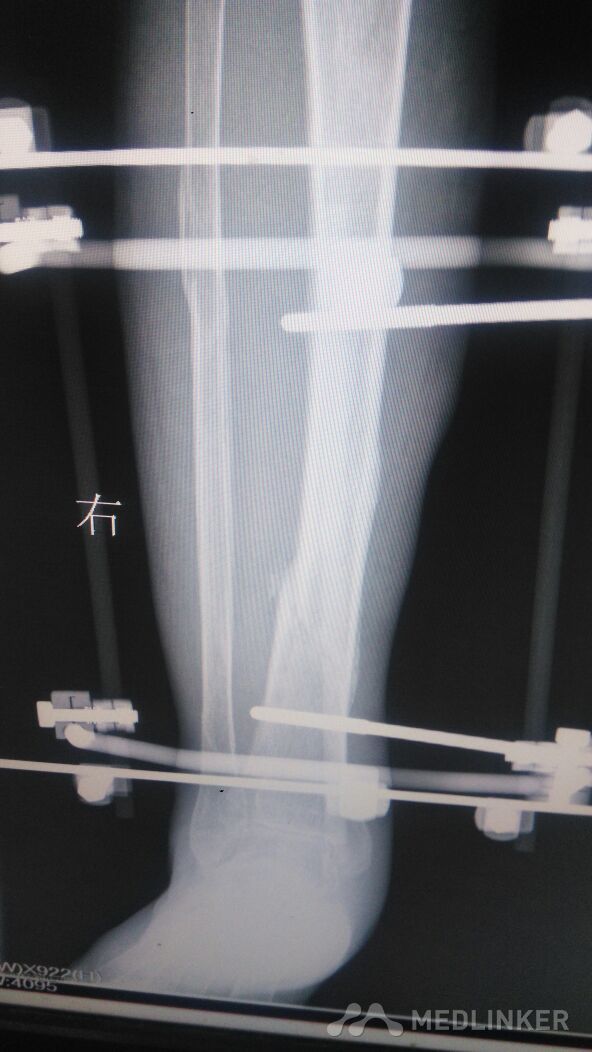

右胫腓骨骨折手术后。

右小腿术后。可见外架针外露。局部皮肤发黑。无渗出。无红肿热痛。

胫腓骨骨折术后10月,右小腿肿胀,压痛阴性,叩痛阳性。右踝关节活动受限。

右胫腓骨骨折,手术外架治疗后。

外架治疗,时间长。病人痛苦多。厌倦走路,很不方便。以致踝关节活动受限。有什么好办法吗?